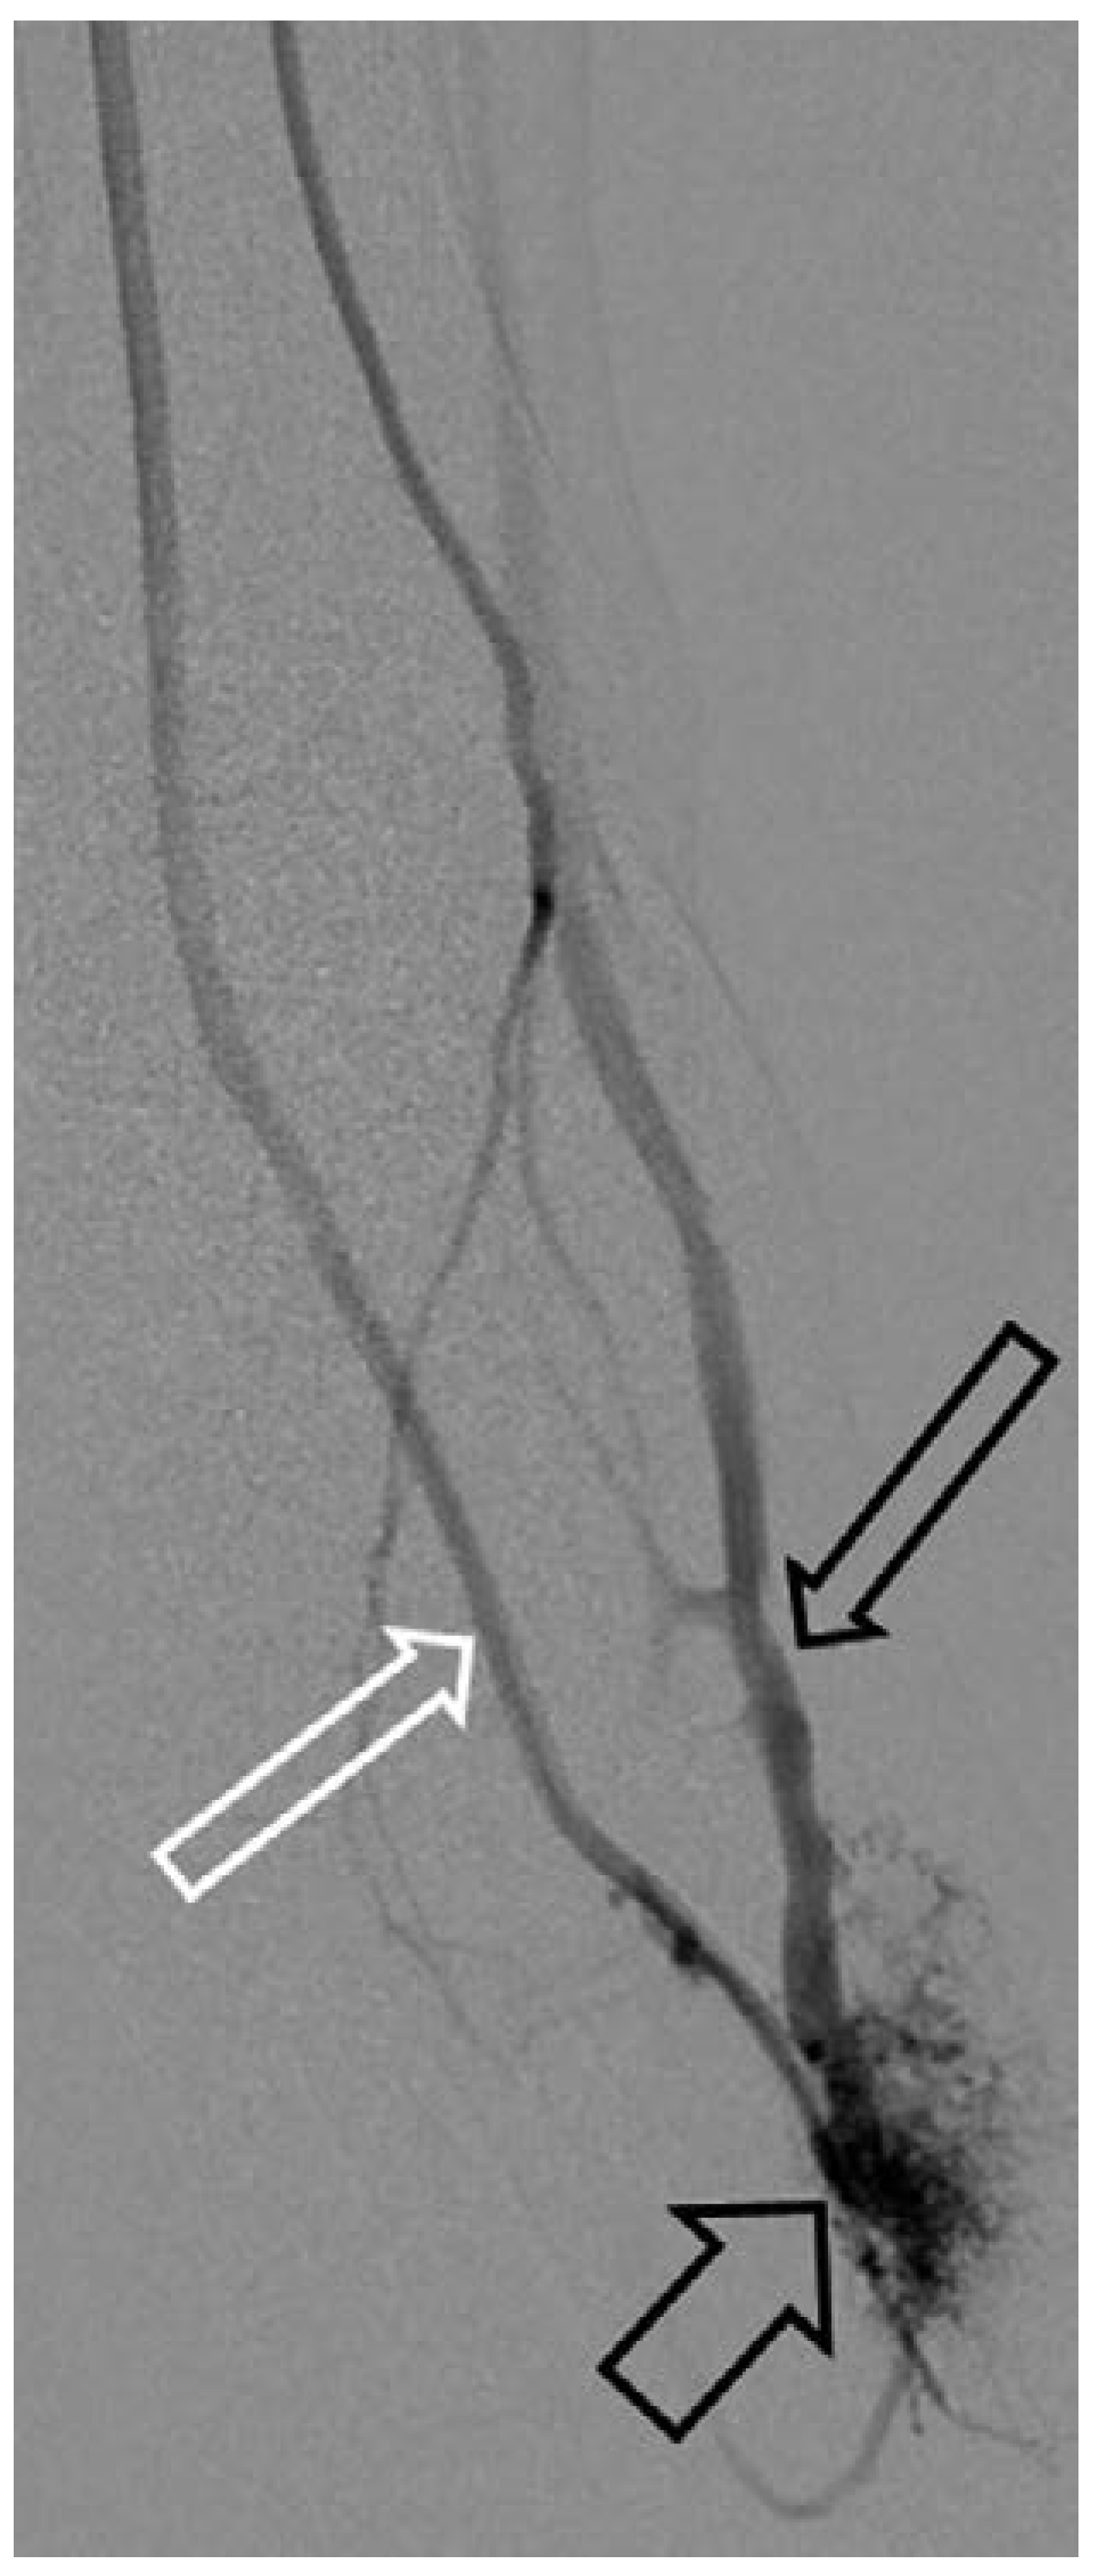

Kapillär-lymphatisch-venöse Malformation mit Überwuchs (Klippel-Trénaunay-Syndrom)

Arteriovenöse Malformation